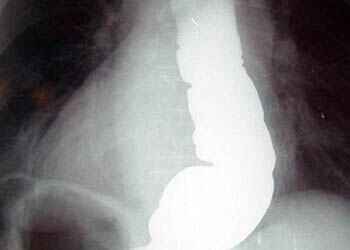

Более точная визуальная оценка возможна при проведении рентгеноконтрастной диагностики с использованием бариевой взвеси. На итоговом снимке отчетливо прослеживается тень деформированного пищевода и аномально узкий участок в непосредственной близости от входа в желудок.